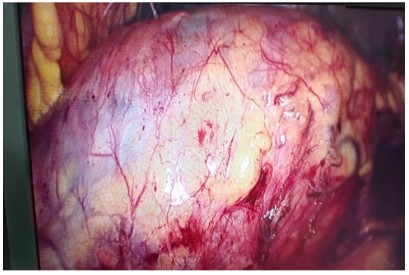

As the cystic lesion was very large so patient underwent for surgery, operative exploration revealed a large firm cystic mass Figure 3 from tail to head of pancreas reaching up to spleen. Pancreatectomy and splenectomy was done. The pancreas, spleen, omental tissue were sent to histopathology laboratory.

Figure 3: Intraoperative cystic lesion of Pancreas.